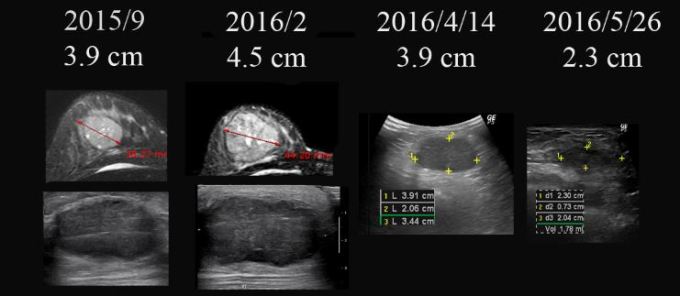

• 2015년 9월 유방암 발견  3.9 cm. 민간요법

• 2016년 2월 유방암 더욱 커짐  3.9cm  —-> 4.5 cm

• 2016년 2월 – 3월  #2차  AC  (adriamycin+cyclophosphamide) 요법 시행

• 2016년 3월 29일  본원 내원 종양  5cm 가량 약간 커졌음

• 2016년 4월 14일  본원  한약조치 이후  5cm의 종양  3.9 cm로 줄어들음

• 2016년 4월 15일  tamoxifen + 한방약물조치

• 2016년 5월 9일  1차  taxol  항암 시작함.  3.9cm(2016/4/4)  —-> 2.3cm (2016/5/26)

• 2016년 7월 8일  3차  taxol  항암 마침.  방사선 치료 의뢰

• 2016년 8월 – 9월 방사선 치료

• 2016년 9월 8일  2.3cm(2016/5/26) —-> 1.13cm(2016/9/8)

• 2016년 10월 13일 약 10mm  x 2mm의 종양의 괴사된 흔적 남아 보임

• 2017년 1월 16일 종양 완전소실  4.4×2.1mm의 흔적남음

• 2017년 5월 26일 초음파상 종양완전소실  2.4mm의 양성으로 보이는 흔적남음

• 수술 시행하지 않고 한약과 tamoxifen 요법을 지속함